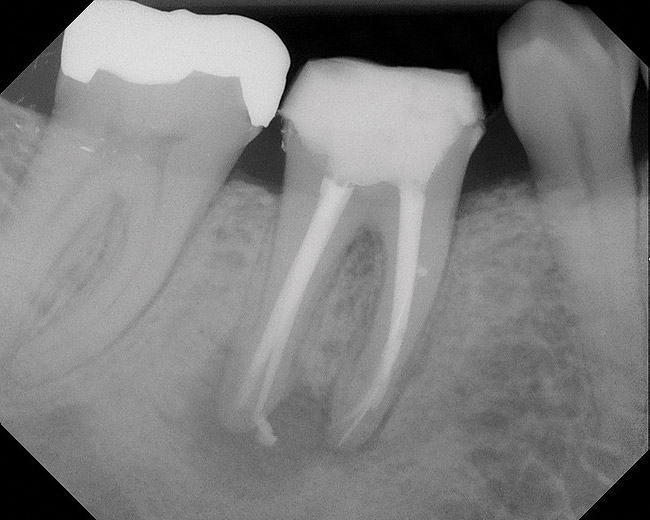

As mentioned, all risk factors associated with both root canal and implant therapy must be carefully considered. Comprehensive clinical and radiographic assessments are necessary to evaluate the patient's risk factors associated with his or her particular case (Figure 1, Figure 2 and Figure 3). The primary risk factors for implants can include smoking, bone quality, and systemic health. For endodontic therapy the primary risk factors are related to the anatomic root complexity, failed root canal treatment with significant technical defects manifested as iatrogenic events, less-than-optimal periodontal status of the tooth (due to a subsequent risk of vertical fracture), and a clinician's lack of experience with regard to the case's complexity. A strong correlation exists between failed root canal treatment and a lack of coronal seal after treatment. This is highly relevant in treatment planning. Often, endodontically treated teeth fail not because they were treated inappropriately and need extraction, but rather, because they have been left unsealed and assaulted by bacteria after the endodontic therapy, causing subsequent long-term clinical failure (Figure 4 and Figure 5).

While not elaborated on here, it is noteworthy that there are a number of additional treatments for resorption that have been suggested in the literature, including calcitonin,27 Emdogain,24,28 and Alendronate (third-generation bisphosphonate in treating EIRR)29 (Figure 6, Figure 7, Figure 8, Figure 9, Figure 10, Figure 11, Figure 12, Figure 13, Figure 14 and Figure 15).